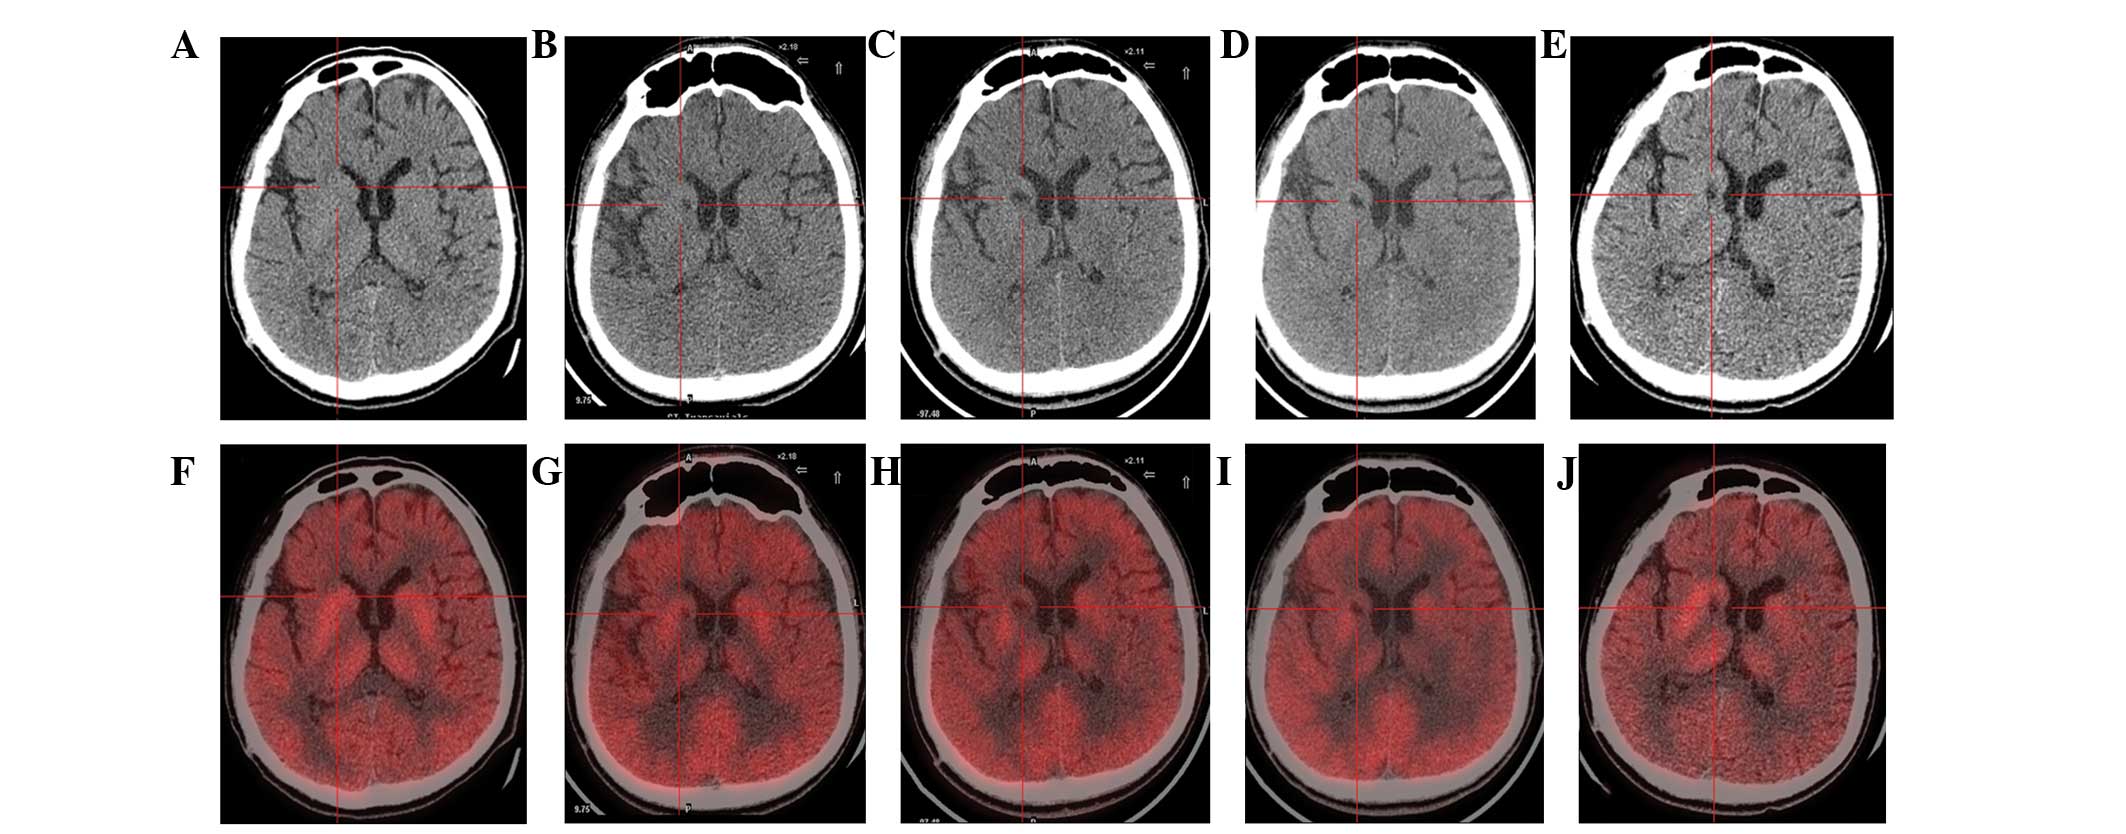

(A) 术前CT显示脑萎缩。

(BE)术后1年、2年、3年、4年CT与术前相比均无明显变化。

(F)术前18F-氟脱氧葡萄糖 (FDG) PET 扫描显示,整个大脑皮层FDG摄取弥漫性减少,细胞核FDG摄取相对高于其他区域。术前1天,豆状核和丘脑的标准化摄取值 (SUV) 平均值/最大值分别为4.3/5.8和3.3/4.5。

(GJ) 神经干细胞移植治疗后分别 1、2、3 和 4 年的 18F-FDG PET 扫描显示,双侧植入部位的豆状核和丘脑对 18F-FDG的摄取增加(红十字)与植入前相同部位进行比较。 豆状核和丘脑的SUV*平均值/最大值在 1、2、分别是术后3年和4年。 该结果表明移植后葡萄糖代谢比移植前稍高。

CT(图1b-e)和MRI(图2b-d)扫描显示4年随访期间没有显着变化。 手术前1天(图1f)和手术后1、2、3和4年(图1g-j) 获得18F-FDGPET扫描。术后双侧植入部位豆状核和丘脑18F-FDG摄取值较术前增加。这一结果表明,自移植以来,葡萄糖代谢逐年略有增加。